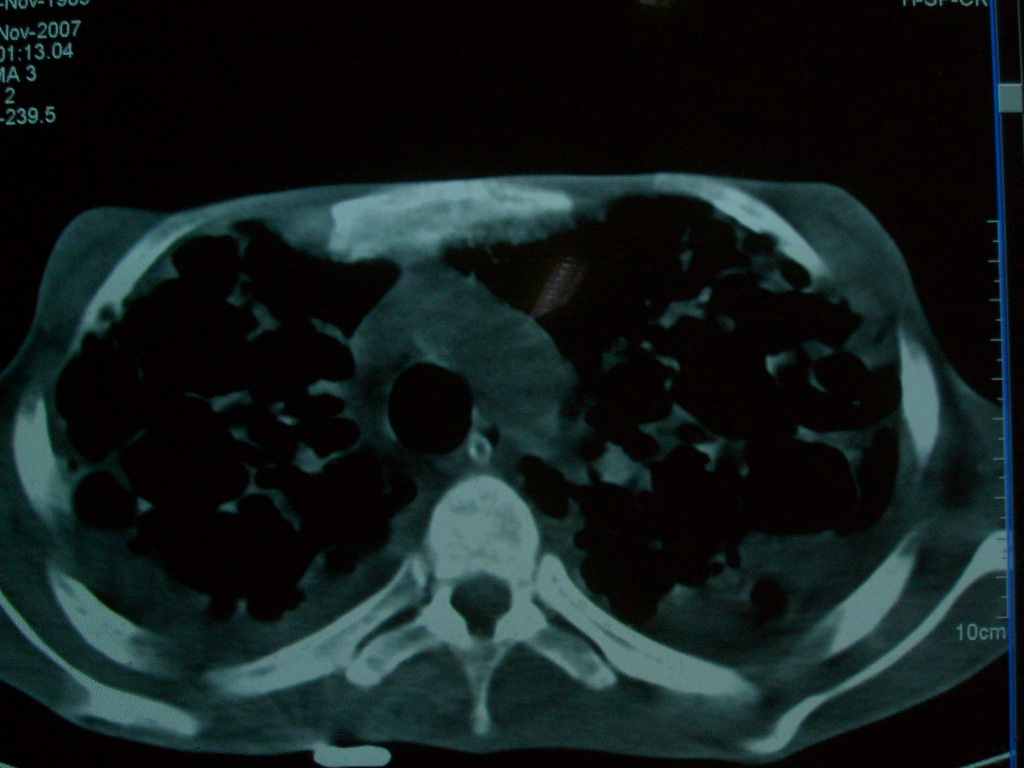

标题: CT10510:男.18岁,咳嗽咳痰两月.(有病理) [打印本页]

标题: CT10510:男.18岁,咳嗽咳痰两月.(有病理)

双肺布满大片状实变及网格状结节影,内参杂大小不等的气囊及空气支气管征,心脏增大。考虑:1 全身结缔组织疾病—系统性红斑狼仓?2 肺泡蛋白沉积症合并感染!

双肺布满大片状实变及网格状结节影,内参杂大小不等的气囊及空气支气管征,双侧胸膜腔少量积液,双下肺近膈面透亮度尚可,病人较年轻,病变较重(不知为什么上胃管?)考虑:1.胶原病肺部改变,2.组织细胞病x。结合实验室检查。

首先考虑组织细胞x病。两肺中上肺野多发囊腔,中下肺野内见多发小结节,并可见肺间质增厚。患者是男性,年龄较小。胶原性病变比较多见的类风湿、系统性红斑狼疮和硬皮病临床和影像均不是很支持,类风湿和系统性红斑狼疮的肺部表现最常见的是胸腔积液,硬皮病可见食管的扩张。

肺内多发斑片状、结节状、融合大片状及网格状影,多发薄壁空腔影,胸膜肥厚,纵隔、气管右移,考虑ⅲ型肺结核,多发空洞,继发肺间质纤维化。

双肺结核并播散.患者以肠梗阻入院,手术为肠结核.术后咳嗽做ct检查.